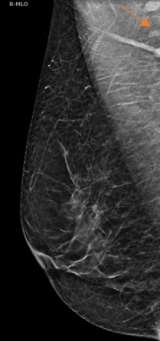

Case: Axillary Lymphadenopathy  Figure 1

Figure 1. MLO view demonstrating benign axillary lymph nodes with radiolucent hilar notch (arrow).

The axilla is partially imaging during mammography and axillary lymph nodes are commonly seen. Evaluation of lymph nodes on mammography involves assessment of laterality and lymph node morphology. Benign axillary lymph nodes (figure 1) are oval in shape, typically measuring less than 2 cm, with a preserved fatty hilum which appears as radiolucent notch on mammogram. Increased lymph node size or density can be abnormal, requiring additional evaluation1. In the case of abnormal lymphadenopathy, attention should be made to whether the lymph nodes are unilateral or bilateral as this can help narrow the differential diagnosis1,2.